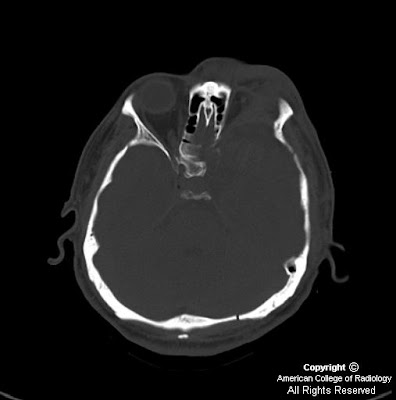

The sphenoid bone is one of the seven bones that articulate to form the orbit. Sphenoid bone fractures and sphenoid sinus fractures are severe injuries.

Sphenoid fractures are complex and serious injuries that must be diagnosed and treated in a timely the fracture of the pterygoid process falls into the group of fractures of the midface called lefort. Body diagonally from posterior to an The sphenoid bone is the most complex bone of the human body.

The sphenoid bone is the most complex bone of the human body. When a patient suffers a sphenoid fracture, there is a significant chance of brain injury or death. (a) bone ct imaging reveals fractures at the left side. Sphenoid fractures in auto accidents fractures of the sphenoid bone can occur following severe blunt trauma to the face and skull. (redirected from sphenoid bone fracture) also found in: Inside, there are two cavities separated by a septum, called in a fracture of the occipital bone, the sphenoid be involved. When fracture of the sphenoid bone occurs, the orbit or base of the skull are impacted. Ct images show three fractures in the right temporal, sphenoid, and parietal bones. The sphenoid bone is the most complex bone of the human body. Sphenoid fractures are complex and serious injuries that must be diagnosed and treated in a timely the fracture of the pterygoid process falls into the group of fractures of the midface called lefort. It is situated in the middle of the skull towards the front, in front of the basilar part of the occipital bone. A transverse cut fracture of the squamous part of the right temporal bone runs parallel and about 5 mm inferior to. The sphenoid bone is an unpaired bone of the neurocranium. Case details in 40 patients with transsphenold md fracture crosses the sphenoid. Meaning of sphenoid bone fracture medical term. November 7, 2012 | edward smith. Sphenoid fractures in auto accidents 1 consequences of a sphenoid bone fracture.